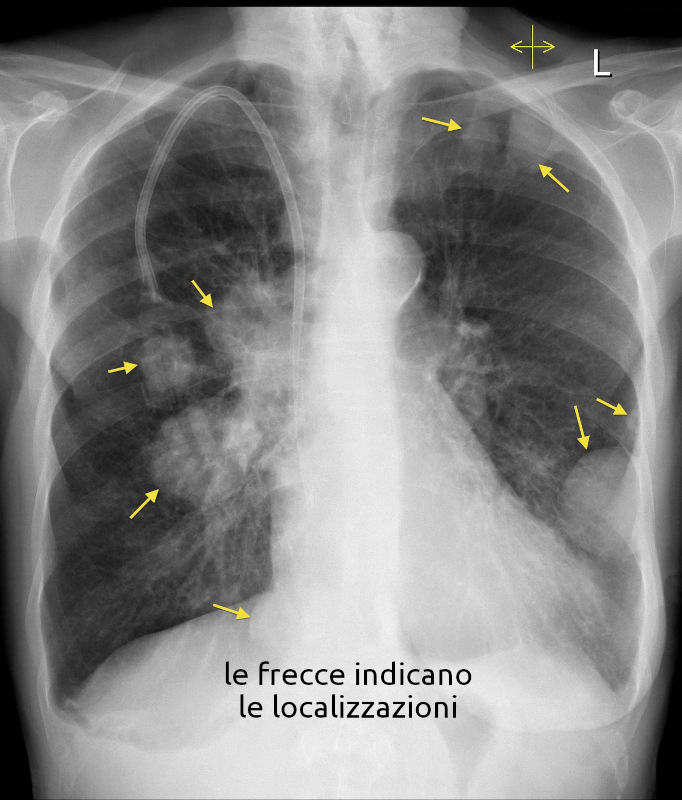

Metastasi polmonari

- Descrizione: Cancro del Polmone che compare dopo un altro cancro verificatosi in altra parte del corpo o altra parte dei polmoni.

La presenza di una sola localizzazione ha a che fare con una specifica persona, mentre se le localizzazioni sono multiple, ha a che fare con se' stessi.